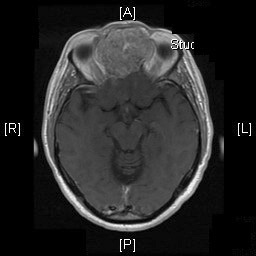

Clinical informationThe patient was a 54 year-old man who came to our clinic with the chief complain of a swelling between his eyes for 18 months. He reported frequent headache, changes in vision including double vision and decreased ability to smell. There was also minor changes in taste and dizziness but he did not report any syncope events. Physical examination revealed widening of nasal bridge and hypertelorism. His facial expression, motility, and strength are preserved. The pupils are equal, round and reactive to light. A CT scan and MRI was performed and demonstrated a large cystic mass as illustrated below. A biopsy was performed through the nasal cavity which yielded small fragments of spindle cell neoplasm with no high grade features demonstrated. Based on the biopsy result, the mass was excised and yielded the following representative images.

Radiologic Images of the Case: CT scan demonstrated a large midline mixed density mass with fat density that occupies the ethmoid sinus with extension through the cribiform plate into the inferior portion of the anterior cranial fossa. The mass is 5.1 x 3.2 cm in greatest dimension (Panel A). Bone windows of CT scan demonstrated bone expansion suggestive of remodeling (Panel B). On MRI, spoiled gradient recalled (SPGR ) post contrast images showing mass is either avidly enhancing or bright on T1 precontrast. (Panel C). The mass hypointense signal intensity compared to brain parenchyma with surrounding areas of increased signal (suggestive of entrapped mucus) on T2 weighted images (Panel D and E).